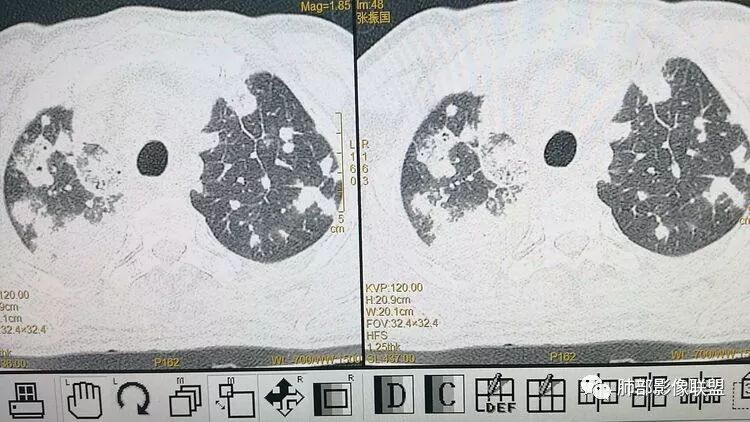

南边:胸膜下,类圆形,边界清,内有坏死,典型的反晕征,支气管壁增厚不明显,支持血道来源脓毒栓子所致梗死、感染

血道来源没问题

左下叶大片类似病灶

Lotus:不能除外肺炎克雷伯三生石上:考虑真菌丽:双肺胸膜下散在结节状及斑片状高密度,密度不均,伴反晕征,首先考虑炎性病变,曲霉菌可能大Shelia:双肺多发结节,大片实变还有胸膜下楔行影,以胸膜下分布为主,有晕和大反晕,左肺实变区有空洞空泡,叶间裂下坠,结合病史,考虑感染,支持血源性感染,说明病原菌有嗜血管,结合肝内病灶,会不会是真菌合并细菌感染,毛霉或曲霉合并肺克?THINKER:急性起病,2DM,蛋白低,CT:双肺多发结节`斑片影,胸膜下为主,伴反晕征,与血管关系密切,考虑血源性,CT肝低密度,首选糖尿病→肝脓肿→肺克,鉴别毛霉。

王秀仙:双肺多发结节及结块影,边缘清晰,呈反晕征,左肺上叶大片实变,密度不均,下缘膨隆,其内可见残留肺组织,肝脏可见低密度,考虑肺克。鉴别毛霉。崇军:高热,感染症状,影像多发结节,反晕征明显,糖尿病,真菌放在第一位,杰克金毛,毛霉菌可能。Yiren Sishui(厶水伊人):肺克,鉴别毛霉菌感染;一米阳光:中年男性,急性起病,双肺散在结节状及斑片状高密度影,以胸膜下明显,没有坏死,密度不均,考虑血播来源,肺克可能,鉴别,金葡,曲霉毛勤香:双肺多发结节斑片状影,呈反晕征,左肺上叶舌段大片状影,叶间裂下坠,糖尿病患者,急性起病,考虑感染性变,首先肺克,代排真菌类曲霉毛霉等,肝脏也有病灶,一元论。小景:糖尿病、肝脓肿?肺内多发结节,反晕,与血管关系密切。考虑肺克。